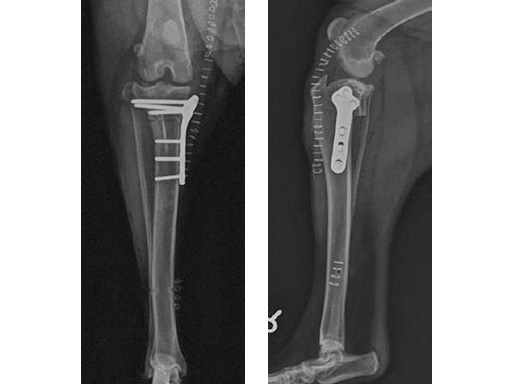

The tibia plateau leveling osteotomy (TPLO) procedure dynamically eliminates cranial tibial subluxation associated with cranial cruciate ligament (CCL) disease in the dog, and thereby stabilizes the knee joint during locomotion. CCL rupture in the dog is similar to ACL injury in humans.

The standard saw and jig are designed specifically for use when performing tibial plateau leveling osteotomy to assist with location, guidance, initiation, and stabilization of the radial saw cut in medium and large breed dogs.